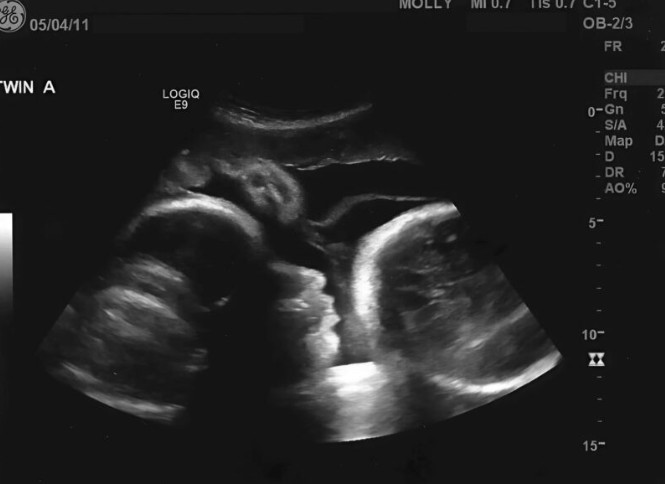

Pitanje koje se nameće jeste zašto Larisa nije potražila medicinsku pomoć ranije. Njena želja da veruje u pozitivan ishod, ali i strah od loših vesti, održavali su je u stanju neizvjesnosti. Nažalost, takva vrsta poricanja može biti veoma opasna. Tek kada je odlučila da poseti ginekologa, Larisa se suočila s realnošću koja je bila daleko od onoga što je želela čuti. Na pregledu, lekar je otkrio da se ne radi o trudnoći, već o ozbiljnom medicinskom stanju koje je zahtevalo hitnu intervenciju.

Kada su rezultati pregleda pokazali da njeno stanje nije trudna, Larisa je bila u potpunom šoku. Simptomi koje je doživela zapravo su bili znakovi ozbiljnih zdravstvenih problema. U tom trenutku, shvatila je da je njena verovanja o čudu bila samo način da izbegne stvarnost. Suočena s istinom, morala je da se suoči sa stvarima koje je ignorisala, dok je njeno zdravstveno stanje postajalo sve kritičnije. Ovo je bio trenutak koji je probudio njenu svest o važnosti zdravstvenih pregleda i proaktivnog pristupa zdravlju.